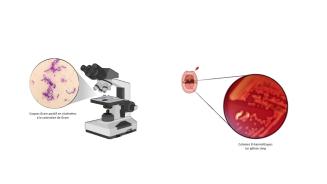

L’Institut européen Plotkin de vaccinologie (epiv.eu) rassemble des équipes de recherche en immunologie et en microbiologie pour lutter contre les maladies infectieuses en Belgique et dans le monde. C’est dans ce cadre que la Dr Gabrielle de Crombrugghe, aspirante FNRS, mène un travail scientifique d’envergure sur le Streptocoque du groupe A, une bactérie responsable de plus d’un demi-million de décès chaque année.

Le Streptocoque du groupe A (ou Strepto A) tue un demi-million de personnes dans le monde chaque année, principalement dans les pays à revenus faibles et intermédiaires, la mortalité la plus élevée étant décrite en Afrique subsaharienne. Cette bactérie est responsable de multiples maladies qui vont des infections superficielles, comme les angines ou les impétigos, aux infections invasives, telles que les méningites, les pneumonies ou les infections du sang. La principale cause de mortalité est due aux complications auto-immunes qu’on observe surtout chez les jeunes patients, lors desquelles le système immunitaire se retourne contre l’hôte et endommage les valves du cœur, entraînant une défaillance cardiaque. Cette maladie auto-immune constitue la première cause de maladies cardiaques acquises chez les enfants et adolescents dans le monde. Elle a presque disparu dans les pays à haut revenu, mais reste une cause majeure de mortalité dans les pays à revenus faibles et intermédiaires. En tant que pédiatre et maman, je m’intéresse depuis plusieurs années à cette bactérie qui touche principalement les enfants et les adolescents. Le Strepto A est une bactérie complexe qui parvient à déjouer les mécanismes de notre système immunitaire, pour laquelle on peine parfois à trouver des traitements efficaces et pour laquelle aucun vaccin n’est encore disponible.